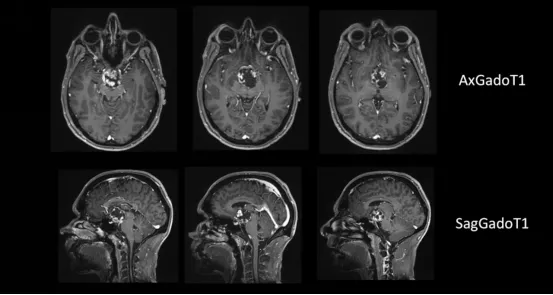

35岁男士,步态紊乱和认知障碍,视野缺损,全垂体功能减退伴轻度高泌乳素血症。

第一阶段,通过神经内镜下经鼻入路进行视交叉和神经减压,从而为后续治疗做准备。然而随着肿瘤的加速生长,出现了新的视觉障碍,和对下丘脑和第三脑室的压迫影响,需要再次手术切除。

第二阶段,经后岩骨入路(或称后迷路经天幕入路)可以很好地暴露肿瘤和周围解剖结构(第三脑室底部和室壁,分支血管,视神经等)。

在此手术视频中讨论并说明了后岩骨入路有关的技术和详细的术中要点,包括横窦-乙状窦连接的后部移位,在天幕切开时如何保护静脉结构,肿瘤切除时第三脑室底部的辨认和保护,细致的多层次闭合等。